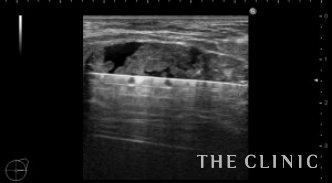

両側に充実性の大きなしこりを認めました。被膜も厚そうです。

いつも通りベイザーで崩します。